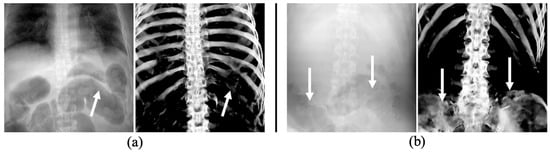

2.3. Pre-Processing: Producing Training Datasets from PMCT Images

3.3. The Performance of Bone Extraction on Real 2D X-ray Images (CXRs)